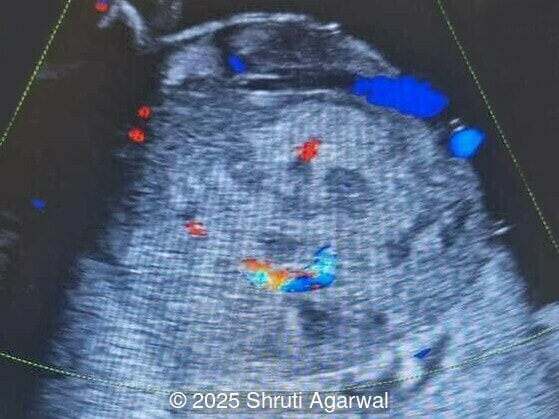

We present a case of fetal anemia due to a giant chorangioma.

- Image 1,2: Large placental tumor is identified with internal vascularity

Prenatal diagnosis depends on ultrasound, however, chorangioma can cause an increase in maternal serum alpha-fetoprotein [3]. Ultrasound examination reveals a hypo- or hyperechoic, well-circumscribed mass, which is usually located underneath the chorionic plate near the umbilical cord insertion, and often protrudes into the amniotic cavity. Color Doppler demonstrates large vascular channels around and within the tumor [6,9]. In cases of giant chorangiomas, echocardiography should be performed to assess cardiac function and measure fetal middle cerebral artery peak systolic velocity for diagnosis of fetal anemia. Regular ultrasounds with Doppler studies are used to monitor tumor size, fetal growth, amniotic fluid volume, and signs of fetal anemia or heart failure. The frequency of exams is based on tumor size and associated complications. With small tumors, assessment may occur every 3-4 weeks, whereas in large tumors, the ultrasound scan may be done every 1-2 weeks [3]. These regular assessments can diagnose conditions that require intervention, such as polyhydramnios, hydrops, or hemolytic anemia.